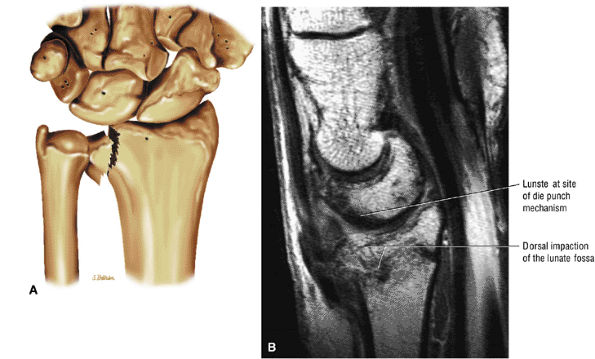

At the site of the radiolunate articulation, the distal articular surfaces of the radius and ulna are usually at the same level (i.e., neutral ulnar variance). Alternatively, the ulna may be relatively long (positive ulnar variance), leading to an ulnar abutment syndrome, or relatively short (negative ulnar variance), as is often seen in Kienböck's disease. The distal radius forms two facets that articulate with the scaphoid and lunate of the proximal carpal row. This articulation of the proximal pole of the scaphoid in the scaphoid fossa is quite congruent, and even a small degree of malrotation of the scaphoid may cause incongruent loading of the articular cartilage and subsequent degeneration (such as that which accompanies a SLAC wrist, as described by Watson and Ryu37). The lunate facet commonly becomes incongruent following distal radius fractures, especially die-punch-type fractures. The interosseous ligaments join the proximal carpal bones at their proximal edges.36